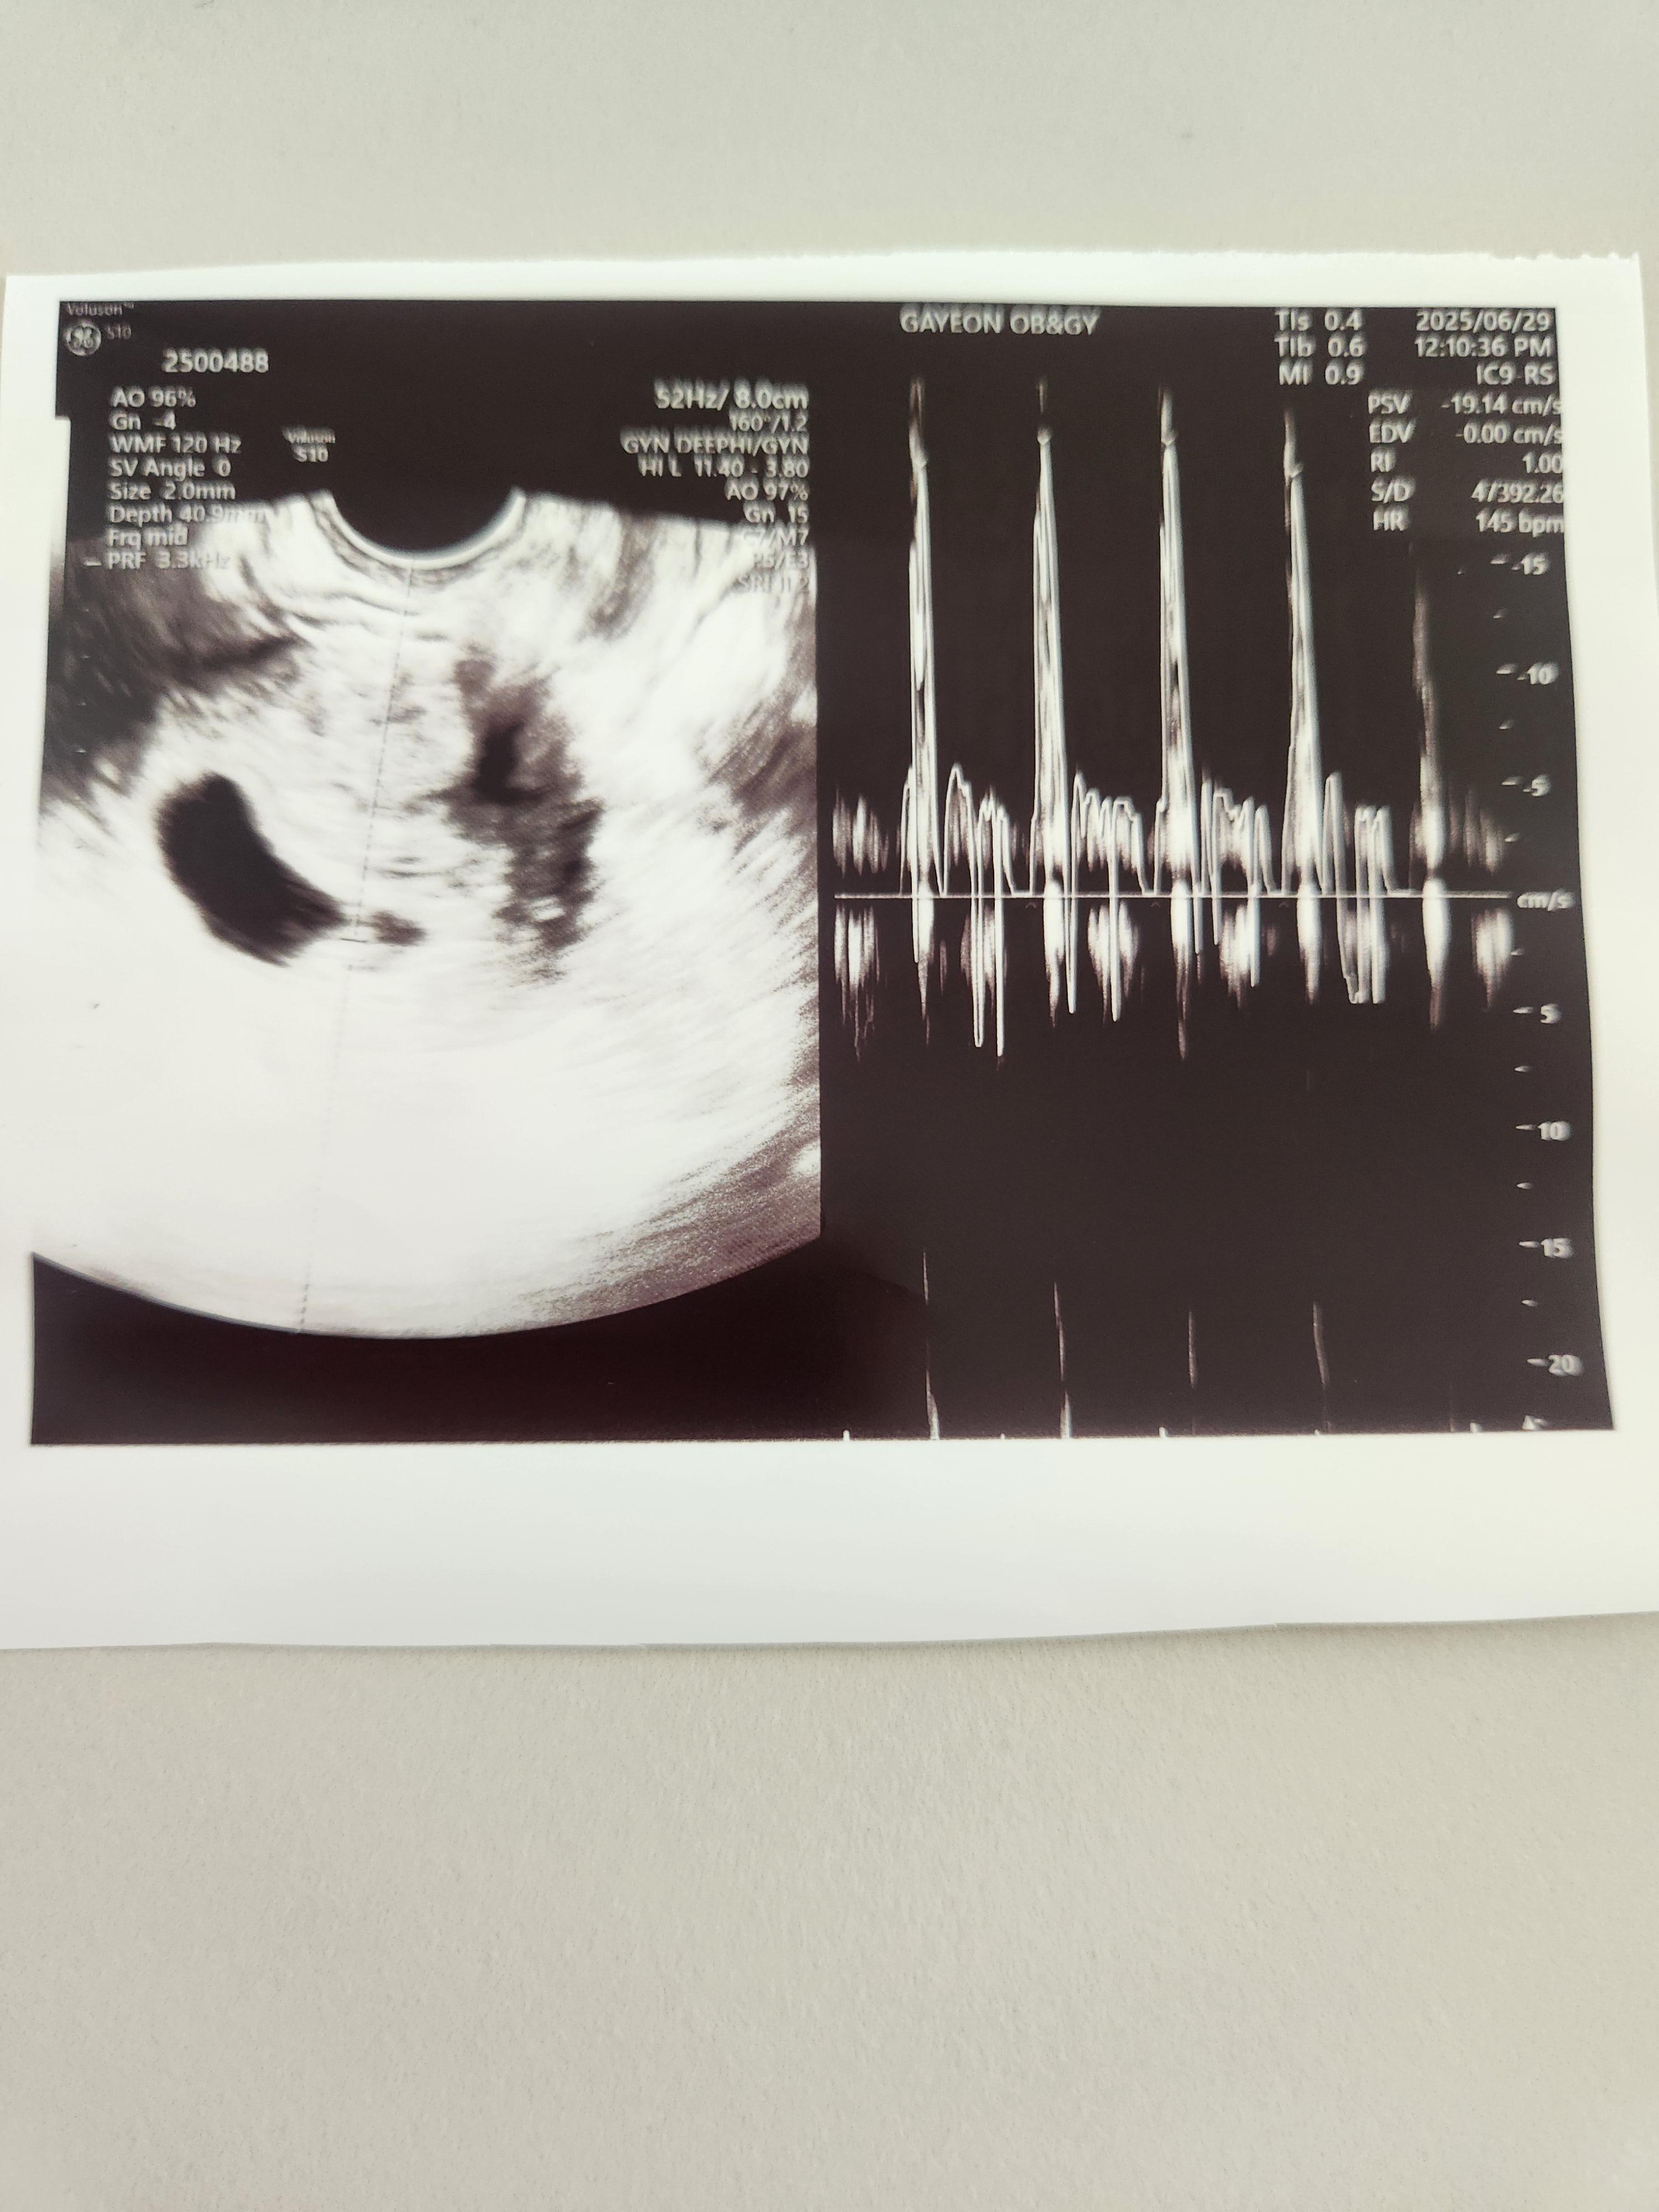

임신 6주 차(6주 4일 차) , 임신 초기 아기 심장소리를 초음파로 확인한 후기에 대해 알려드리겠습니다.

의사 선생님께서 아기심장이 아주 잘 뛰고 있다고 해주셨습니다.

초음파로 아기심장 소리를 들으니 얼떨떨하면서, 이 조그만한 것도 생명이라고 힘차게 뛰고 있구나 라는 생각이 들었습니다.

아기는 아주 건강하게 잘 있다고 하셔서 안심할 수 있었습니다.